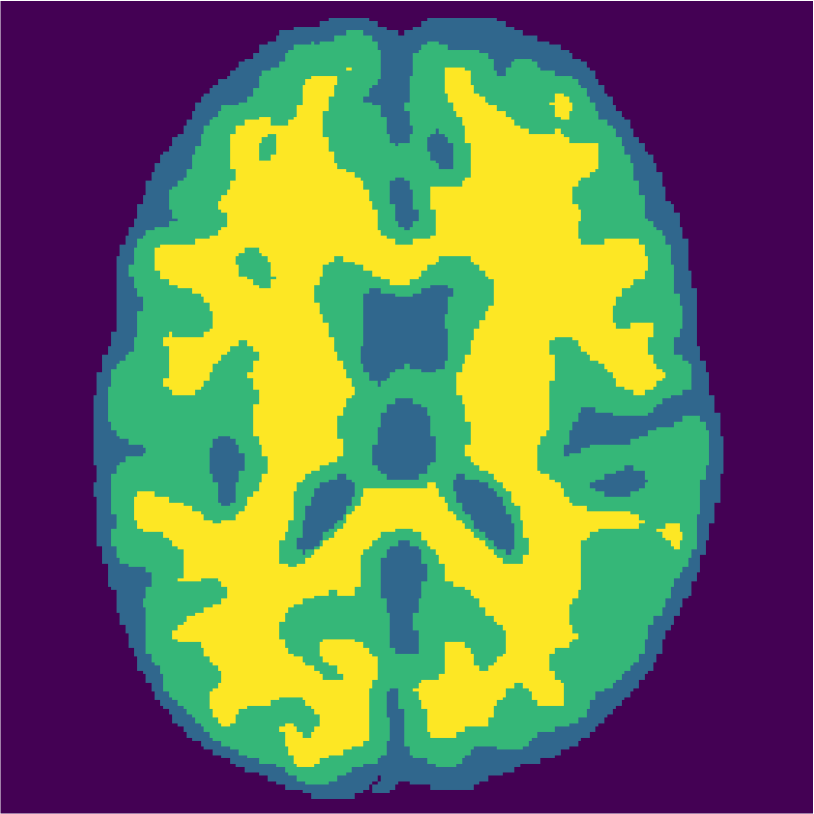

Examples of the segmentation results on one of the target test images are shown in Figure 8 for experiment 2.1, Figure 9 for experiment 2.2, and Figure 10 for experiment 2.3. Examples are shown after using 1 target patch per tissue for training, and after using 100 target patches per tissue for training. The results show that only the mrai-net classifier is able to predict a segmentation that approaches the ground truth with only 1 target patch per tissue for training (error for experiment 2.1 = 0.269, experiment 2.2 = 0.403, experiment 2.3 = 0.320), while the source and target classifiers cannot (source error for experiment 2.1 = 0.667, experiment 2.2 = 0.653, experiment 2.3 = 0.435; target error for experiment 2.1: 0.591, experiment 2.2: 0.614, experiment 2.3 = 0.596). After using 100 patches the source and target classifiers can predict a gross segmentation of WM, GM and CSF (source error for experiment 2.1 = 0.213, experiment 2.2 = 0.384, experiment 2.3 = 0.363; target error for experiment 2.1: 0.205, experiment 2.2: 0.368, experiment 2.3 = 0.368), but the mrai-net classifier prediction shows more details and a lower tissue classification error (error for experiment 2.1 = 0.111, experiment 2.2 = 0.276, experiment 2.3 = 0.284).

In order to test the proposed method on real data, we use the publicly available training data (5 subjects) from the MRBrainS challenge444http://mrbrains13.isi.uu.nl/Figure. The acquisition parameters used for simulating the Brainweb3.0T are based on the MRBrainS acquisition protocol (3.0T scanner, gradient-echo, B0 = 3.0T, = flip angle, TE = 4.5ms, and TR = 7.9ms). Figure 5(c) shows an example of an MRBrainS scan. Again, a brain mask is used to strip the skull.